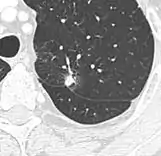

Calcifications and popcorn-like appearance, conferring a diagnosis of hamartoma.[9]

• In case of calcifications, a popcorn-like appearance indicates a hamartoma, which is benign.[3]